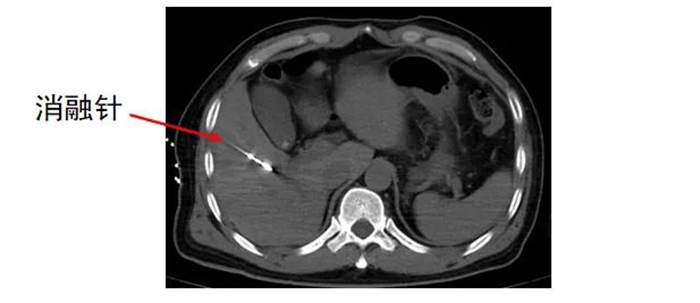

经皮肝恶性肿瘤微波消融术是治疗肝脏恶性肿瘤的局部微创治疗方法,具有创伤小、恢复快、对肝功能影响相对较小等优点。

但如何确保在手术中精准定位,将消融针准确置入肿瘤部位,并根据肿瘤的具体情况,合理控制消融范围和能量,避免损伤周围正常组织,需要医生拥有丰富经验和精准操作技巧,以及较强的判断力、把控力。

齐先生病灶临近大血管、重要脏器。厦门三院专家团队在CT引导下精准定位,经皮穿刺将微波消融针准确置入齐先生肝脏肿瘤部位,然后利用微波能量,使肿瘤组织内的水分子快速振动、摩擦产生热量,从而使局部温度迅速升高,让肿瘤细胞凝固性坏死。整个手术过程顺利,避免了严重并发症发生。

准确插入到病灶内,并避开了门静脉右支及胆,避免了出血、损伤胆囊等并发症。